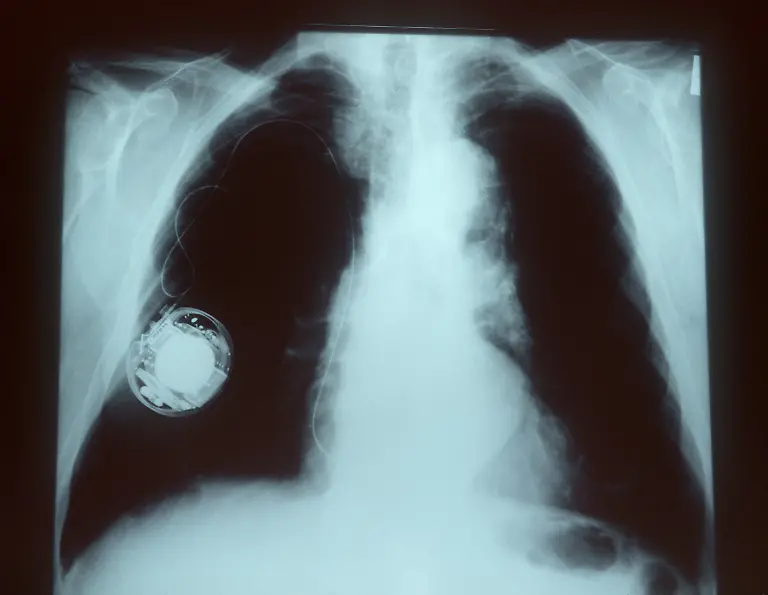

Am 8. Oktober 1958 wird erstmals ein Herzschrittmacher in einen menschlichen Körper eingesetzt. Seitdem helfen die kleinen Kisten dabei, das Herz wieder im richtigen Takt schlagen zu lassen - und retten damit Leben.